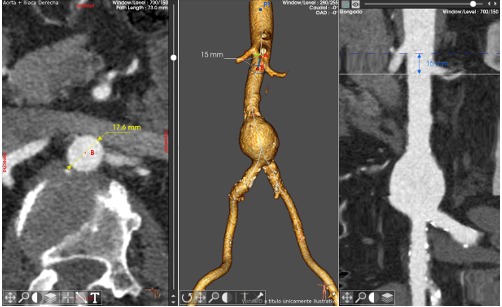

De mayor frecuencia en hombres que en mujeres, principalmente a partir de los 60 años, el aneurisma aórtico abdominal es una dilatación anormal en la parte baja de la arteria principal del cuerpo llamada aorta, arteria principal del cuerpo que se extiende desde el corazón hasta el centro del pecho y al abdomen.

“Esto ocurre cuando las paredes de la aorta se debilitan, provocando un ensanchamiento o abultamiento, el cual si no es identificado a tiempo puede romperse, causando una hemorragia interna grave con consecuencias fatales” , expresó el Dr. Enrique López Ochoa Angiólogo y Cirujano Vascular del en el Centro Médico Dr. Ignacio Chávez en Hermosillo, Sonora.

Afortunadamente, Sonora se consolida como un referente en atención médica al ofrecer tratamientos innovadores de vanguardia, como un procedimiento quirúrgico denominado Reparación Endovascular de Aneurisma Aórtico Abdominal (EVAR), técnica mínimamente invasiva consistente en la realización de pequeñas incisiones en la ingle para introducir un catéter hasta llegar al aneurisma y cubrirlo con un stent-injerto de alta tecnología, conocido como prótesis Aorfix, capaz de fortalecer la pared arterial, reduciendo el riesgo de ruptura y sangrado, ofreciendo así una solución eficaz y segura para quienes enfrentan esta condición de salud.

La prótesis Aorfix es un dispositivo médico diseñado para el tratamiento de aneurismas de la aorta abdominal, especialmente en pacientes de alto riesgo con anatomías complejas, como aortas tortuosas o con angulaciones, donde otras endoprótesis podrían no adaptarse correctamente, y cuyo diseño flexible minimiza el riesgo de complicaciones durante su colocación, además de promover una recuperación más rápida en los pacientes.